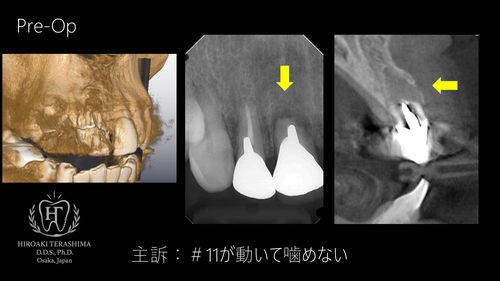

2025/08/2374歳の前歯の抜歯即時埋入~簡単な症例~

◆ 患者情報

根尖病巣・歯根吸収による保存不可能歯を即時インプラントで対応